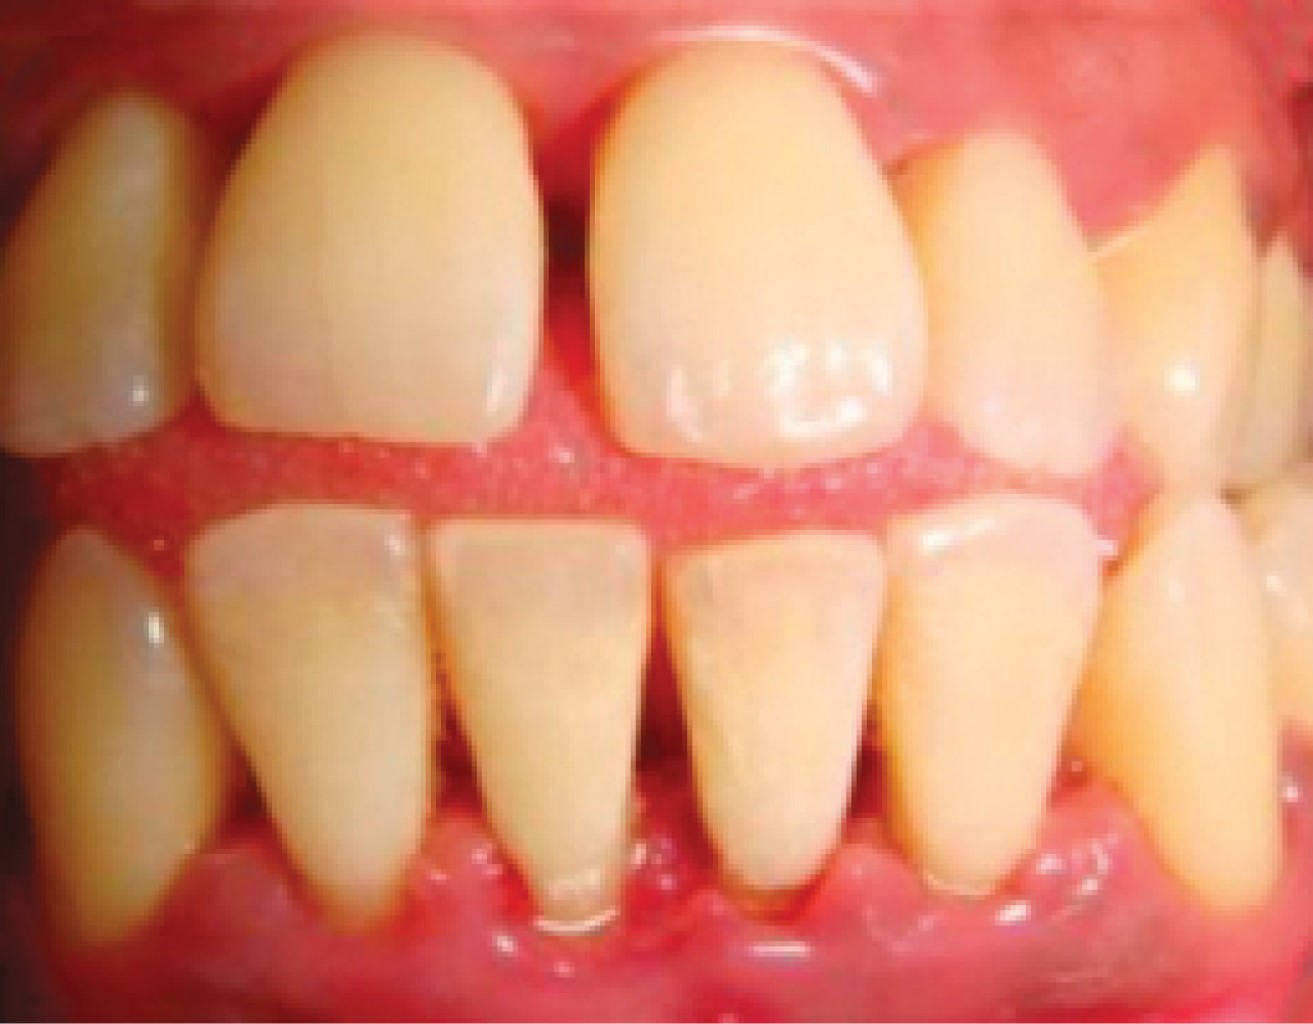

Seis años después acude nuevamente, presentando las siguientes características: agrandamientos gingivales de tipo inflamatorio generalizados, presencia de biofilm microbiano, cálculo supragingival y subgingival, abscesos periodontales, recesiones gingivales, todo esto evidencia un desapego al mantenimiento periodontal. Los niveles de glucemia obtenidos por medio de la toma capilar fueron de 450 mg/dL (Figura 4A-C).